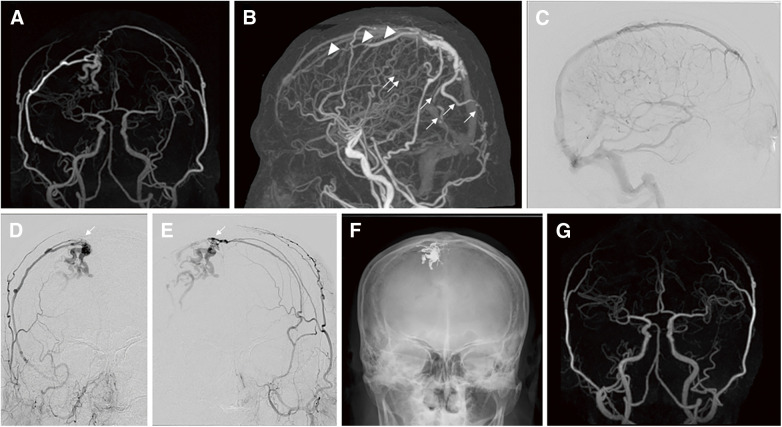

Abstract Image